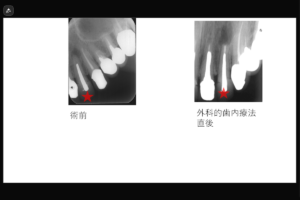

治療内容:上顎右側中切歯 根管治療(穿孔修復、根尖孔外異物除去)

治療のリスク: 残存歯質の厚みによって歯根破折のリスク、経過によっては外科的歯内療法